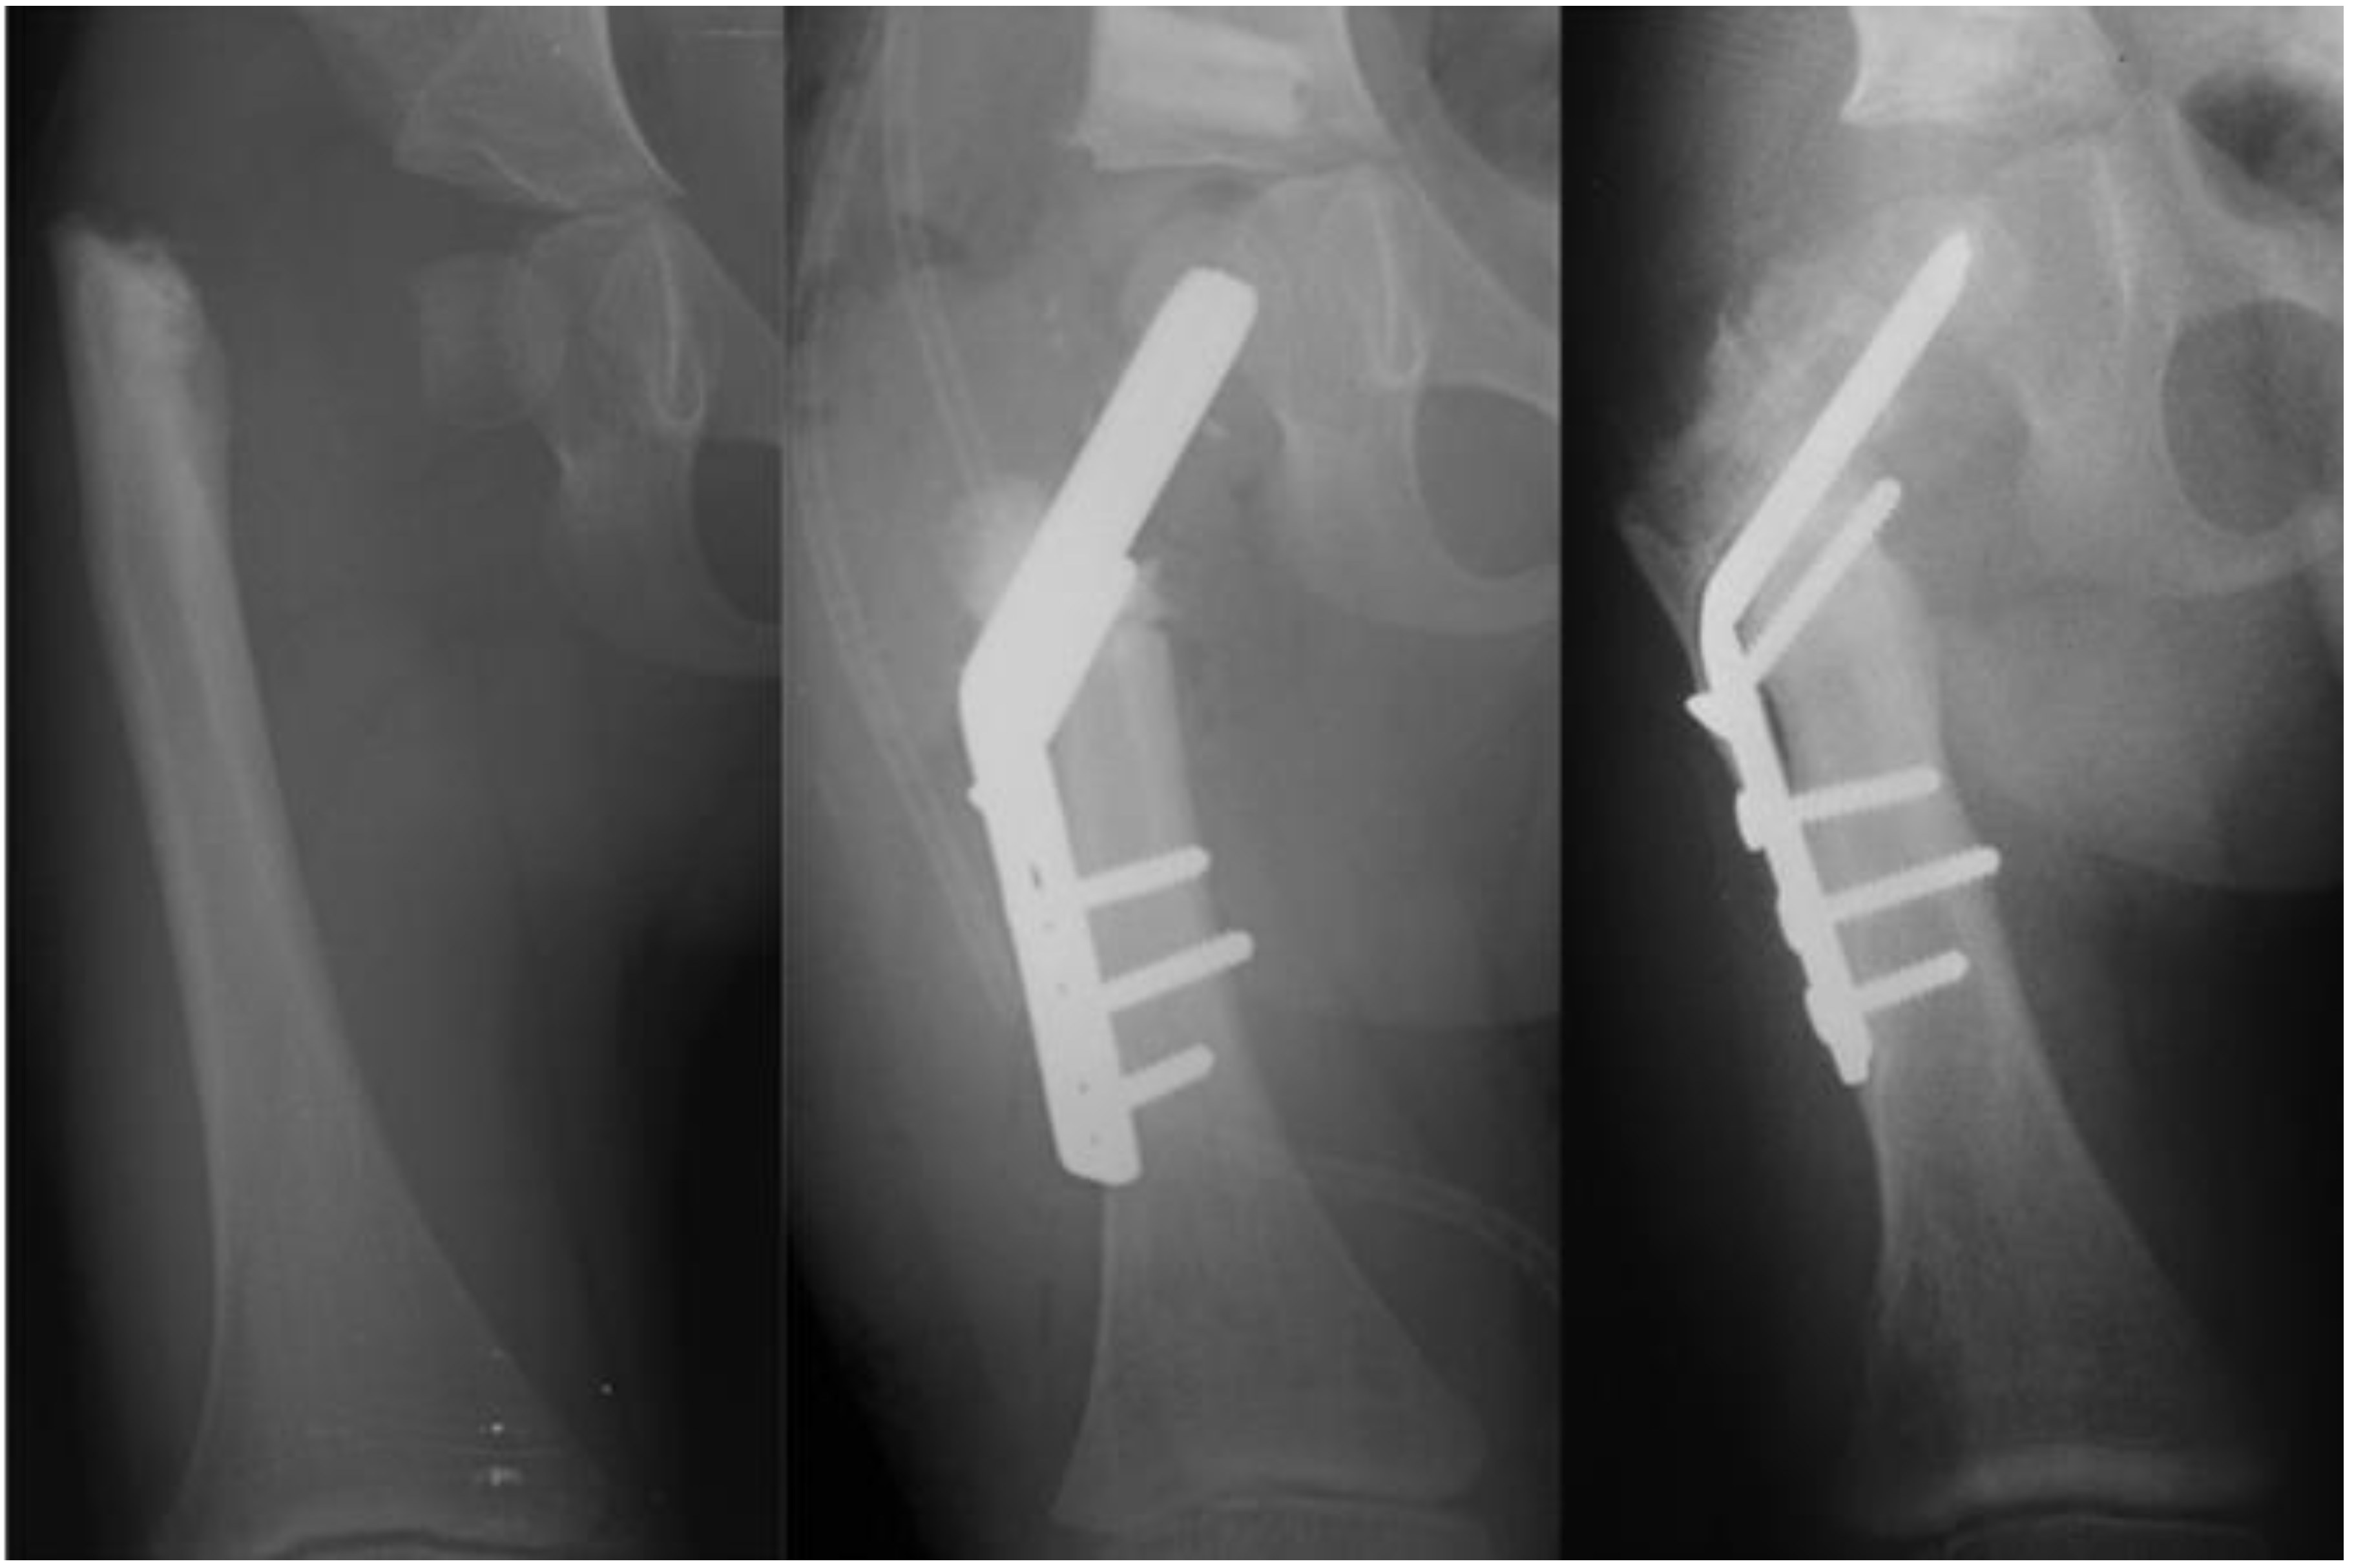

Figure 6.

Type 1b CFD preop (left); immediately after SH procedure with fixed angle device and insertion of BMP2 into superior femoral neck (middle); and three months after SH procedure showing ossification of the superior femoral neck in the region of the BMP2 (right).